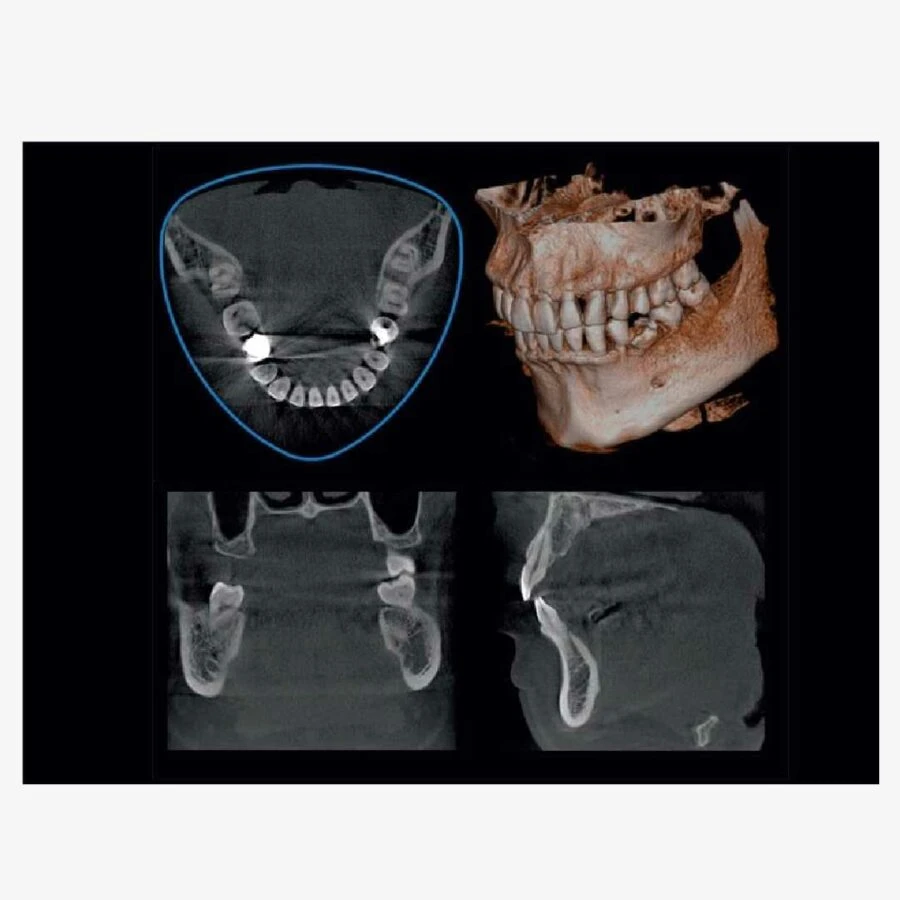

Máy X-quang nha khoa 3D Veraviewepocs R100 đã đột phá đưa ra hình dạng mới của FOV, cho phép đạt được gần nhất hình dạng hàm răng tự nhiên. Việc sử dụng 3D Reuleaux Full Arch FOV cung cấp các hình dáng độc nhất cho việc tạo ảnh toàn bộ hàm.

Trường nhìn máy x-quang nha khoa 3D toàn hàm dạng tam giác

– Với 6 lựa chọn trường nhìn và chất lượng hình ảnh nổi tiếng thế giới của Morita, X550 phù hợp cho các ứng dụng đa dạng trong nha khoa bao gồm phương án cấy ghép.

– Khả năng chụp toàn bộ vòm miệng, giảm liều tia và rất rõ ràng là các đặc điểm lý tưởng cho việc lên kế hoạch cấy ghép và phẫu thuật miệng.